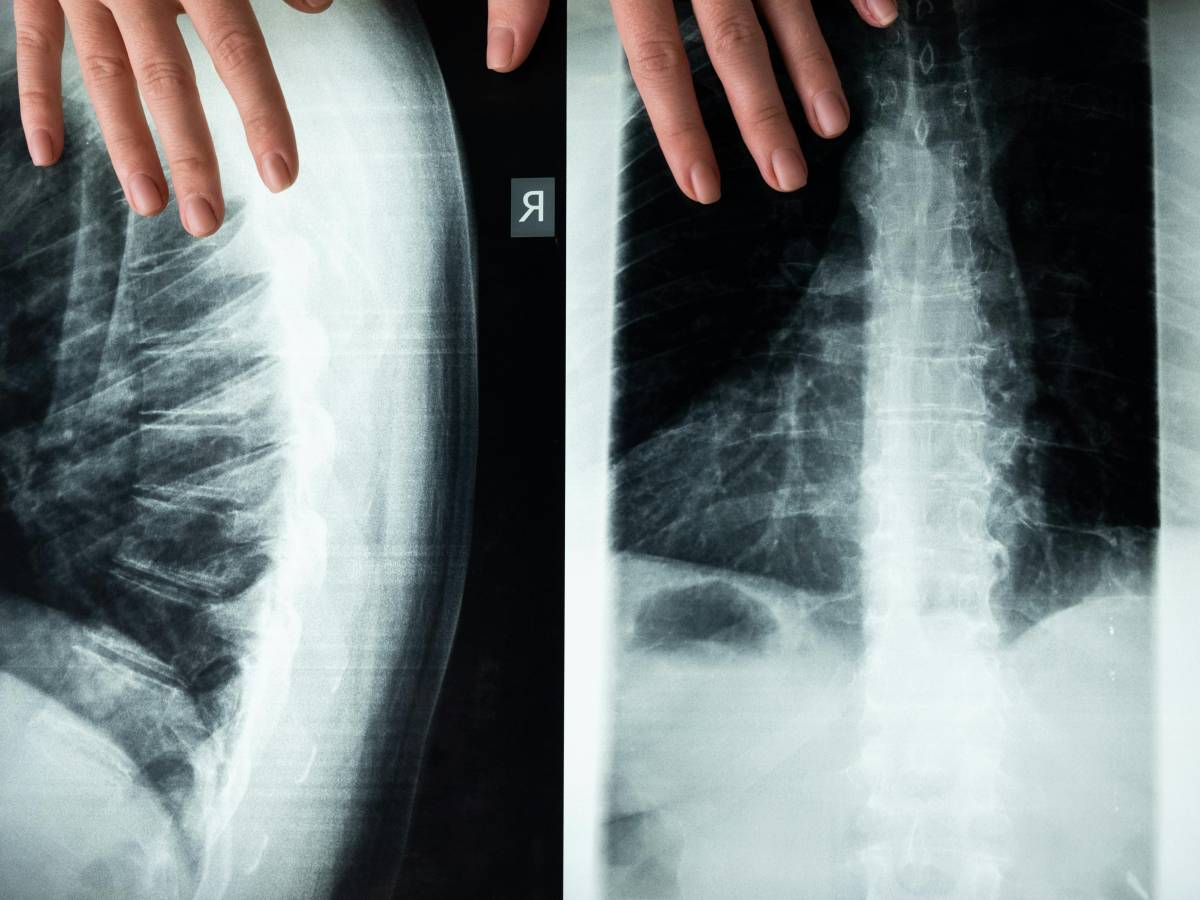

Mieloma multiplo i campanelli d’allarme | il 70% dei pazienti manifesta un dolore alla colonna vertebrale

Il mieloma multiplo è un tumore che interessa le plasmacellule del sistema immunitario. Secondo uno studio recente, circa il 70% dei pazienti con questa condizione avverte un dolore alla colonna vertebrale. Si tratta di un sintomo comune tra le persone affette, che può comparire prima di altre manifestazioni della malattia. La diagnosi precoce resta fondamentale per affrontare questa patologia.

Il mieloma multiplo è un tumore maligno ematologico che colpisce particolari cellule del sistema immunitario, le cosiddette plasmacellule. Si caratterizza per la proliferazione e l’accumulo nel midollo osseo di un anomalo clone plasmacellulare. Dati alla mano, ogni anno in Italia vengono diagnosticati in media 11,1 nuovi casi ogni 100mila uomini e 7,7 nuovi casi ogni 100mila donne. Ad esserne maggiormente colpiti sono gli over 70. Raramente la malattia interessa individui con meno di 40 anni. Il ruolo della componente monoclonale. Le plasmacellule, come abbiamo visto, sono cellule del sistema immunitario derivanti dai linfociti B. Questi ultimi generano gli anticorpi che hanno il compito di proteggere l’organismo dalle infezioni e di aiutarlo a contrastarle.🔗 Leggi su Ilgiornale.it